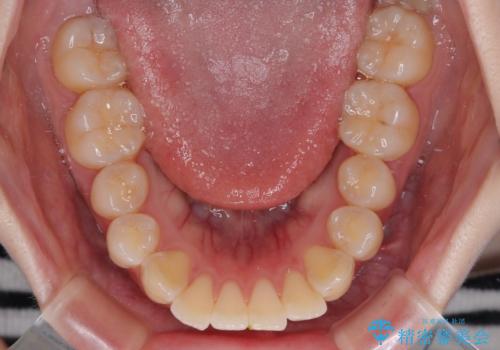

- くちばしのように飛び出した前歯を気にして来院された患者様です。

上下左右の第一小臼歯4本を抜歯して、ワイヤー装置にて矯正治療を行うこととしました。

舌の突出癖により、口元が突出しているだけでなく、上下前歯が非接触となっておりました。

舌のトレーニングをしっかりと行っていただくことで、2年を切って治療を終えるとともに

、上下前歯を接触させることができました。